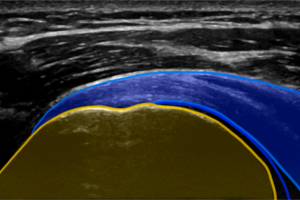

Ultraljud ger både en överlägsen upplösning/detaljrikedom samt möjliggör dynamiska undersökningar i realtid.

Ultraljudsdiagnostik av rörelseapparaten är idag en mycket användbar och tillförlitlig undersökningsmetod som används till akuta skador såväl som långsamt tilltagande överbelastningsskador.

Vid användning av en modern version av ultraljudsutrustning, lik den vi har på MPFysio, fungerar metoden i vissa fall lika bra som magnetröntgen vid undersökning av exempelvis skador i axelns senor, senor i underben och händer m.m.